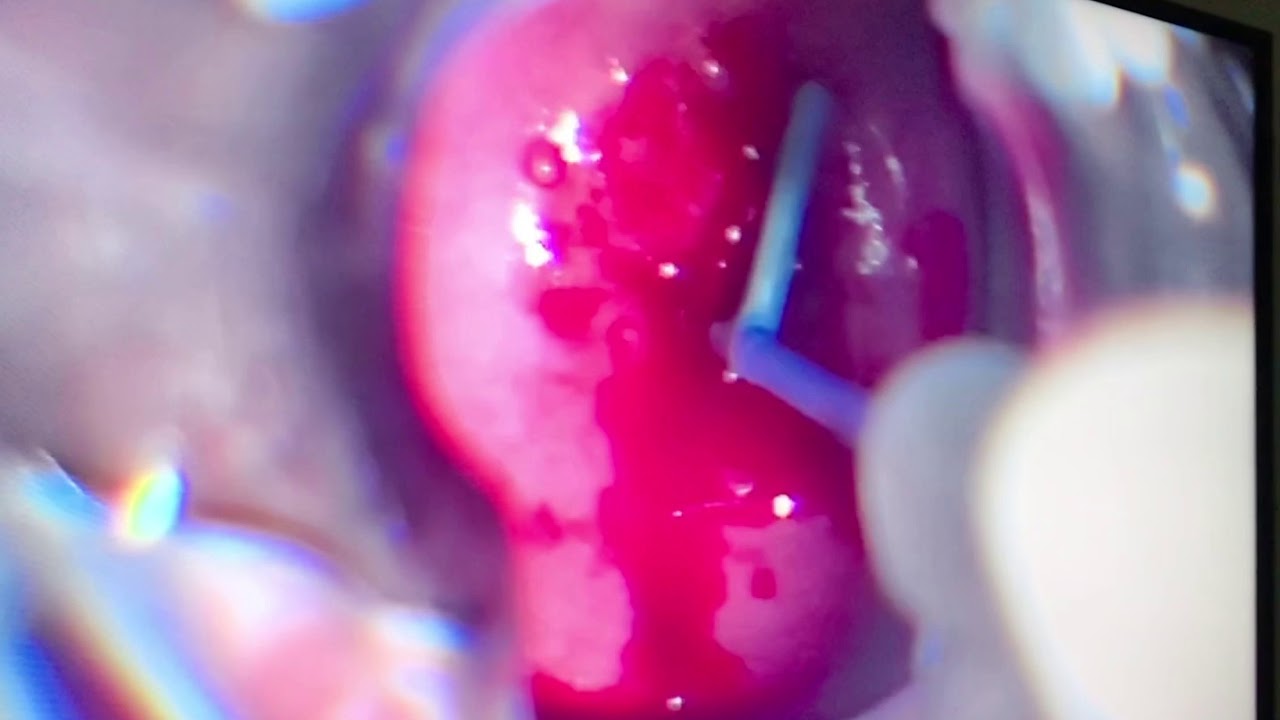

- Endoscopia ginecológica

- Cirurgia ginecológica

- Histeroscopia cirúrgica